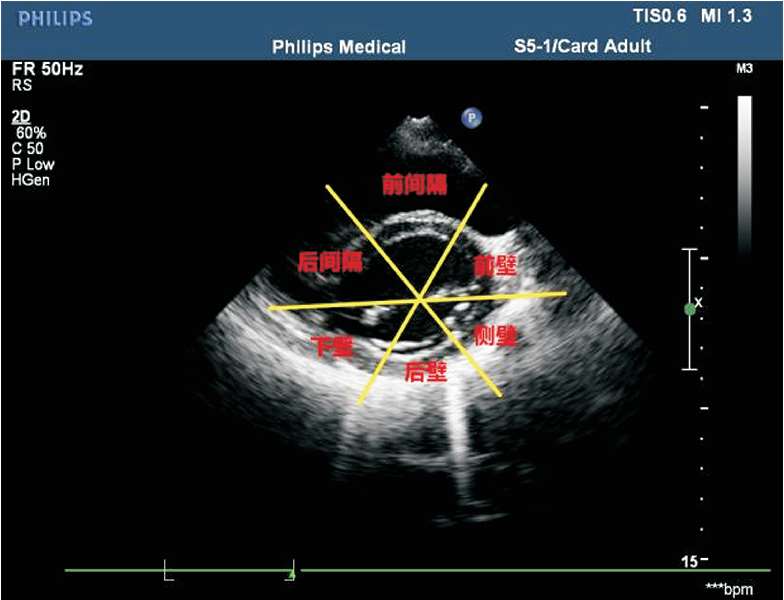

(7)常用的室壁分段方法为16段法。左心室长轴切面将左心室分为3等分:基底段、中间段及心尖段。基底段、中间段短轴切面分为6 等分:左心室前壁、左心室侧壁、左心室后壁、左心室下壁、后间隔及前间隔(见图1-38)。心尖段短轴切面分为4等分:左心室前壁、左心室侧壁、左心室下壁及室间隔(见图1-39)。

图1-38 基底段、中间段短轴切面分6等分